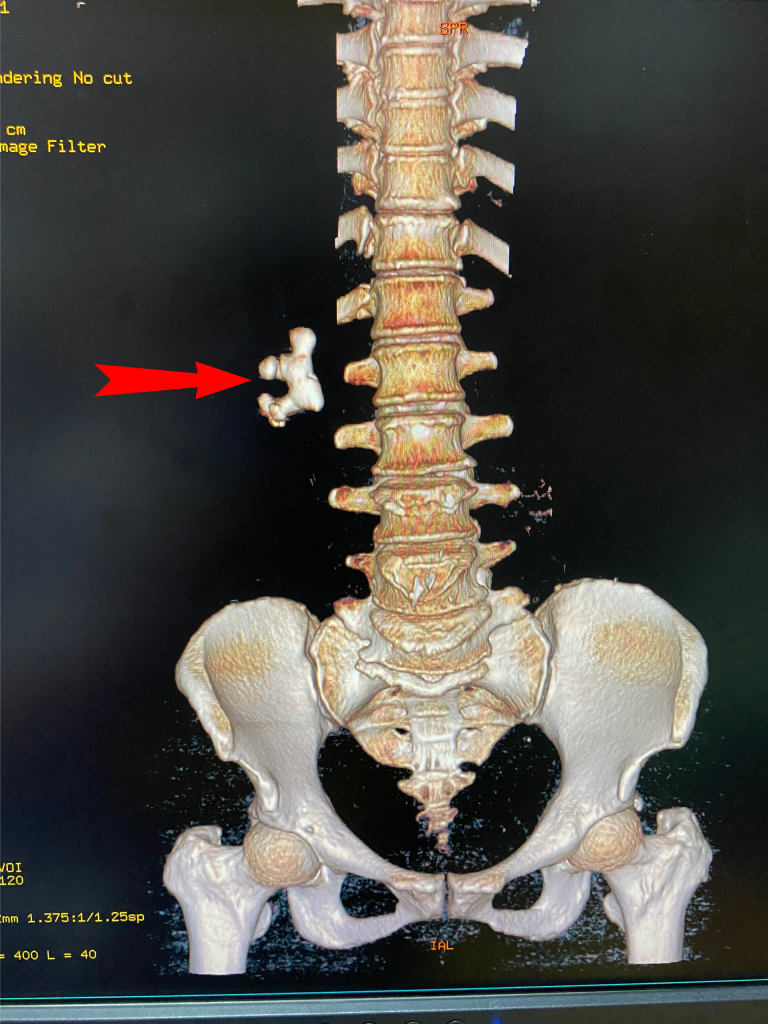

Ngày 25/10/2022, anh B.V.H, sinh năm 1997, ở xã Xuân Viên, huyện Yên Lập, tỉnh Phú Thọ được gia đình đưa đến cấp cứu tại Trung tâm Y tế huyện Yên Lập. Theo lời kể của gia đình, người bệnh đi xe máy bị ngã, sau ngã tỉnh, đau nhức, mất vận động chân trái, […]